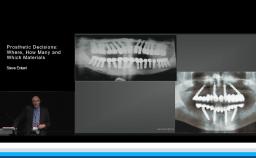

This lecture describes a well documented case series on the effect of different abutment designs for single tooth implant restorations. The long term crestal bone level changes were analyzed retrospectively to understand the good or bad effects of abutment designs and materials. R. Oretti, with his clinical experience, provides clinical recommendations regarding the abutment designs while treating single missing teeth either with a tissue level or a bone level implant. Insights on the abutment material selection, implant-abutment junctional wear, and the ideal abutment contours are explained to achieve the long-term success of the implant restorations.

- recognize the selection criteria and the influence of the tissue level versus bone level implants to achieve long term success

- discuss the types of superstructures in restoring edentulous short spans either by joining adjacent single implant crowns, splinting them together or providing an implant supported bridge